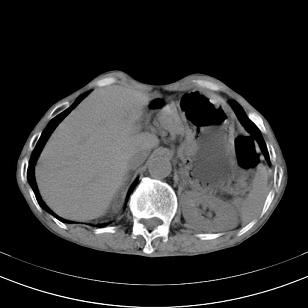

标题: 男,65岁,反复右上腹痛, [打印本页]

标题: 男,65岁,反复右上腹痛,

胃镜提示十二指肠占位